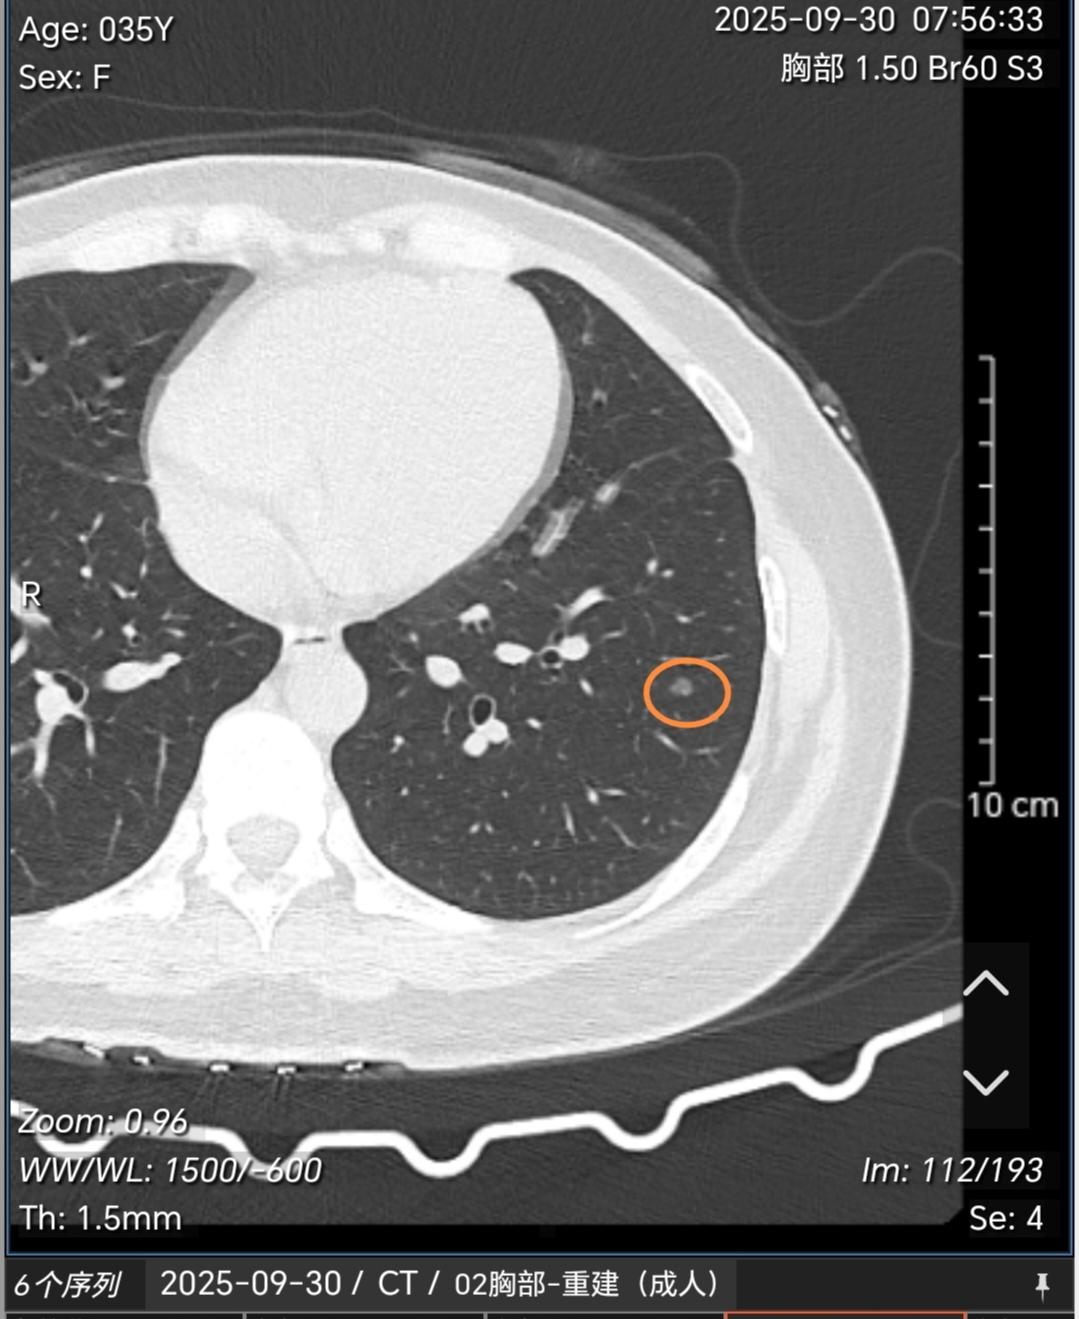

多发磨玻璃结节常见原因有哪些?如何处理?这种多发磨玻璃结节如果经半年左右观察没有明显缩小或消失一般多考虑是肿瘤性的,这类多发肿瘤性的磨玻璃结节最常见的原因就是遗传(基因易感体质),再者就是职业原因接触一些高致癌物质(苯、酚、氡、放射性物质、重金属等)。其他烟、空气污染等所致的肿瘤多见的是单发。那么对于这类结节怎么处理?对于这类多发的,一般手术很难切净,所以建议先观察,后续发现哪个结节有增大再以这个结节为主进行包括手术、消融或立体定向放疗在内的综合治疗策略。